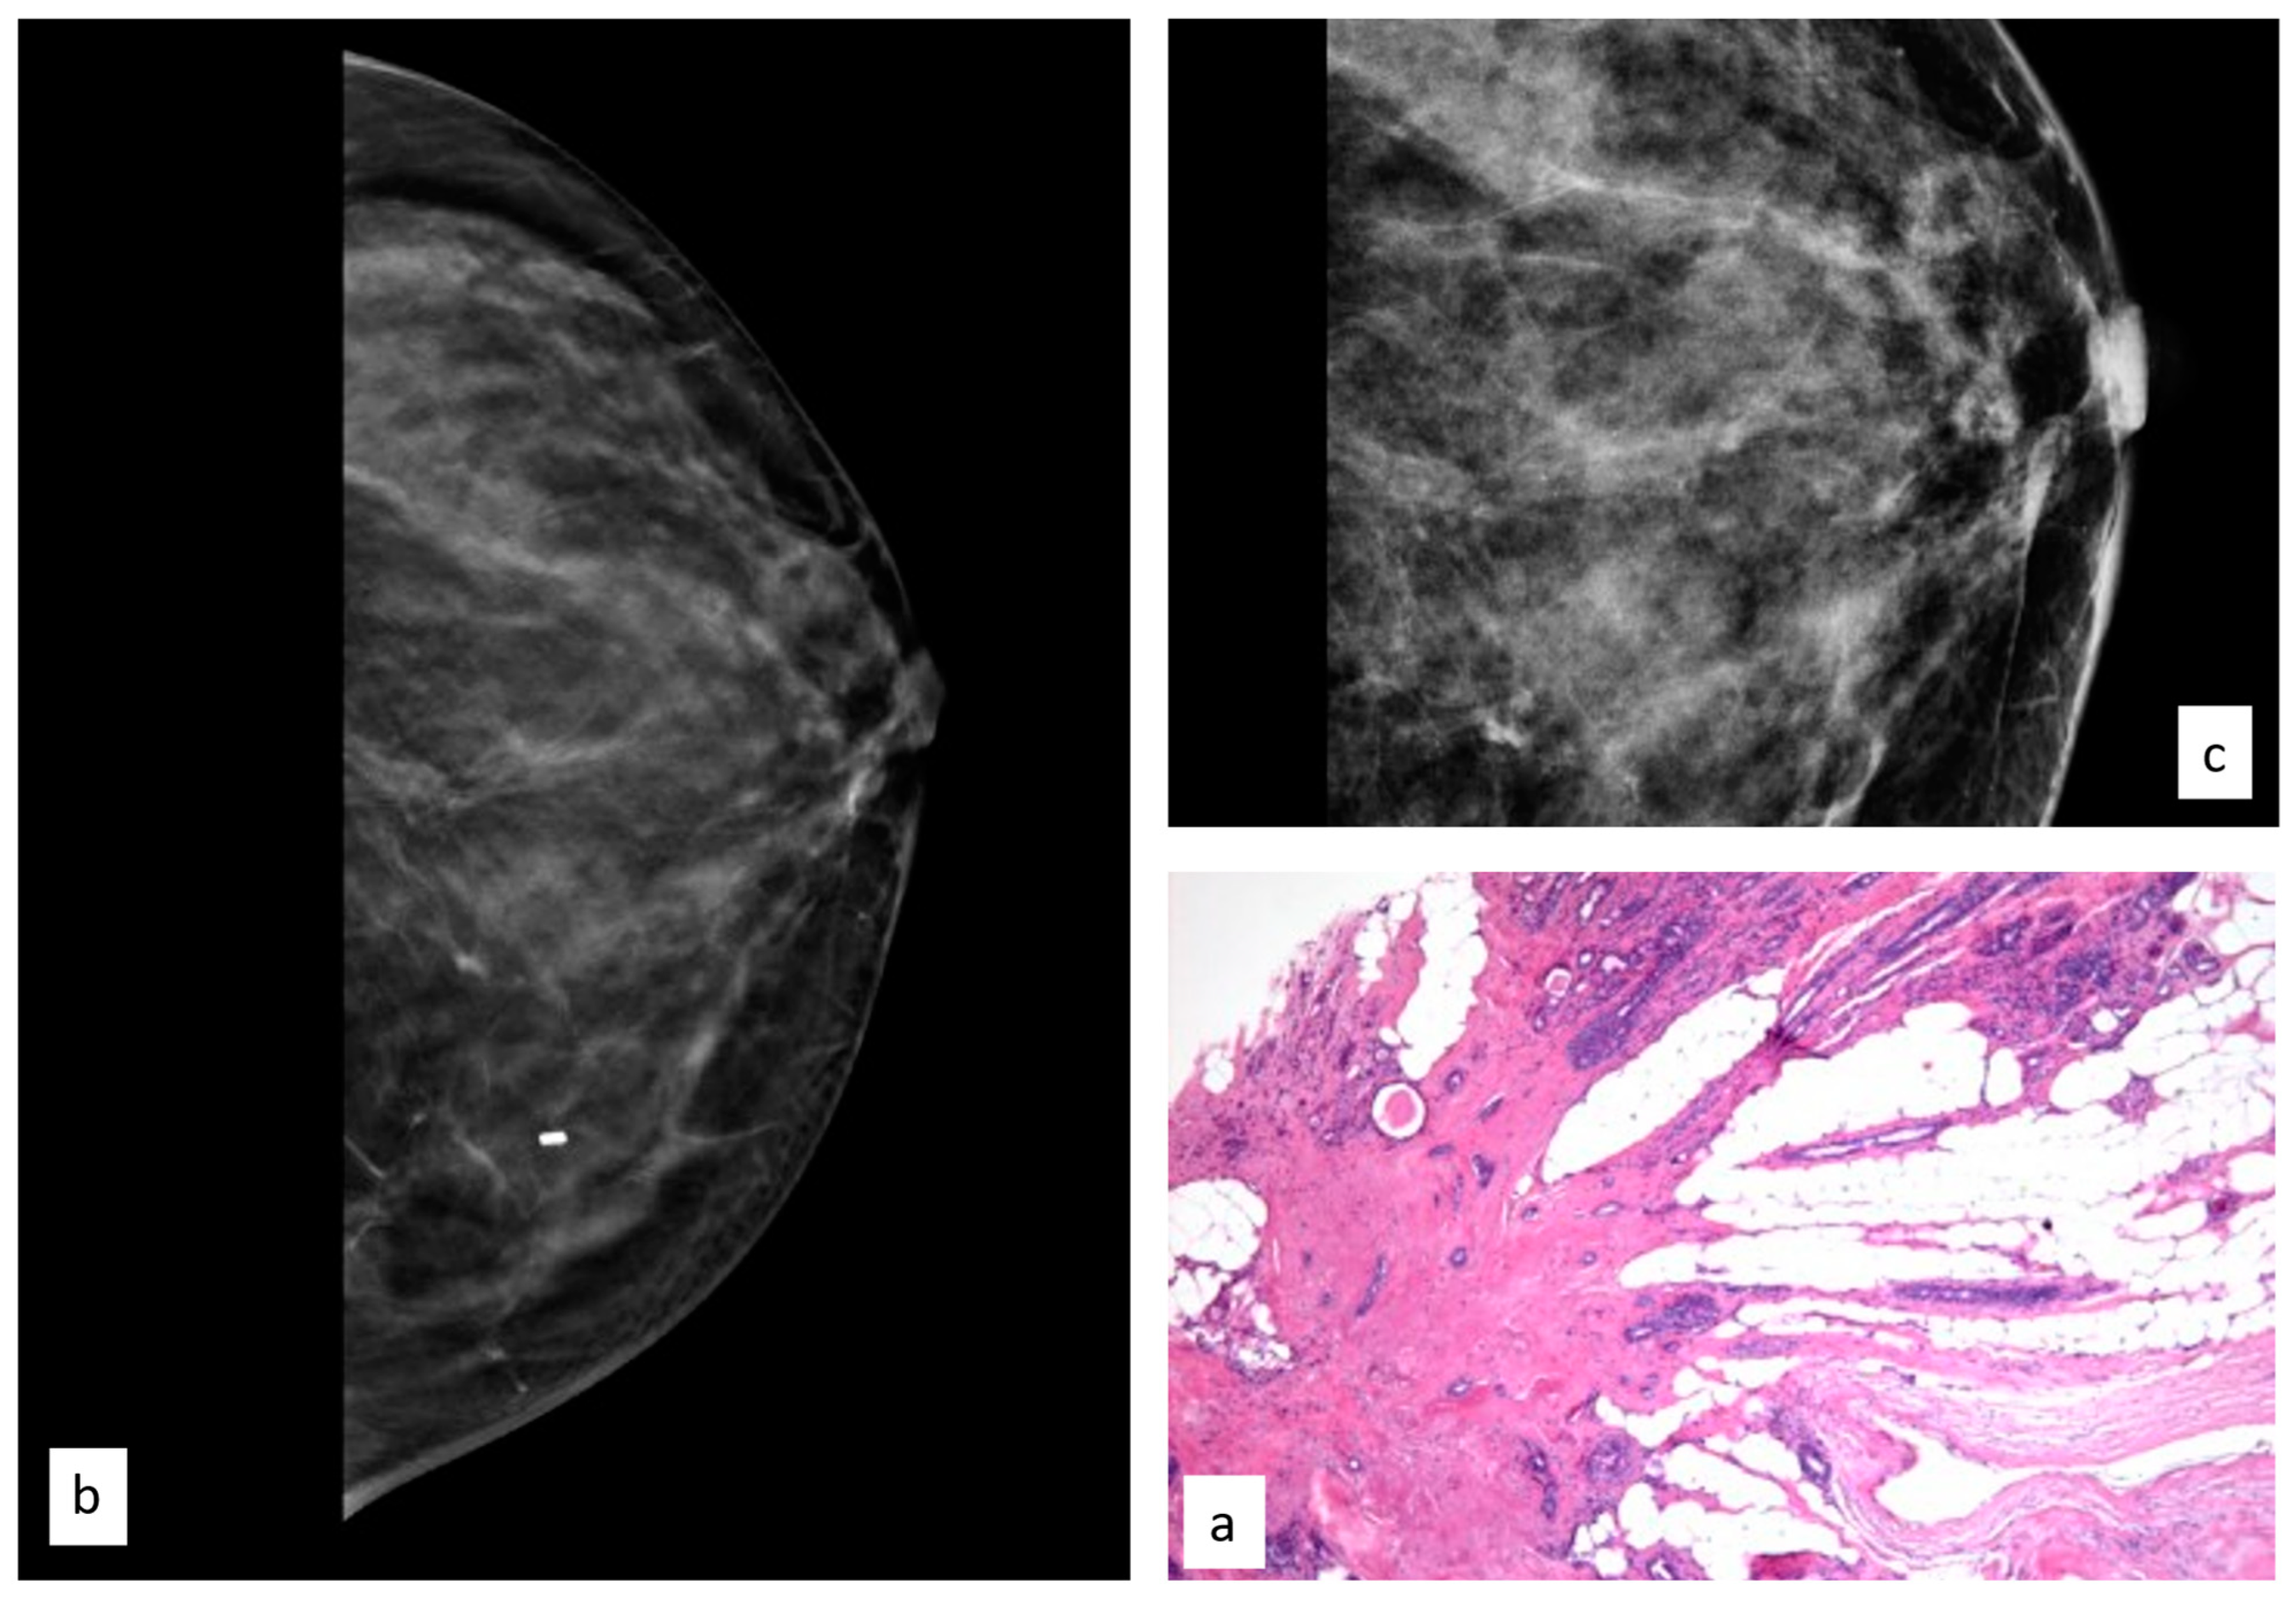

3.3.6. Radial Scar